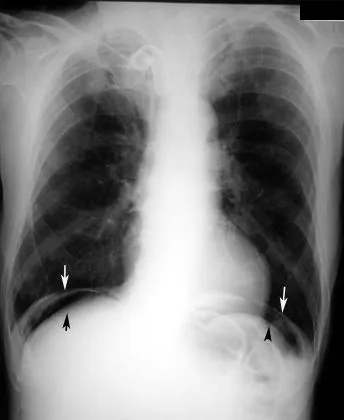

- Diagnosis: Clinical signs of an acute abdomen (rebound tenderness, guarding). Upright CXR or CT scan confirms pneumoperitoneum (free air).

- Imaging: Upright X-ray (free air) or CT scan (abscess, definitive source).